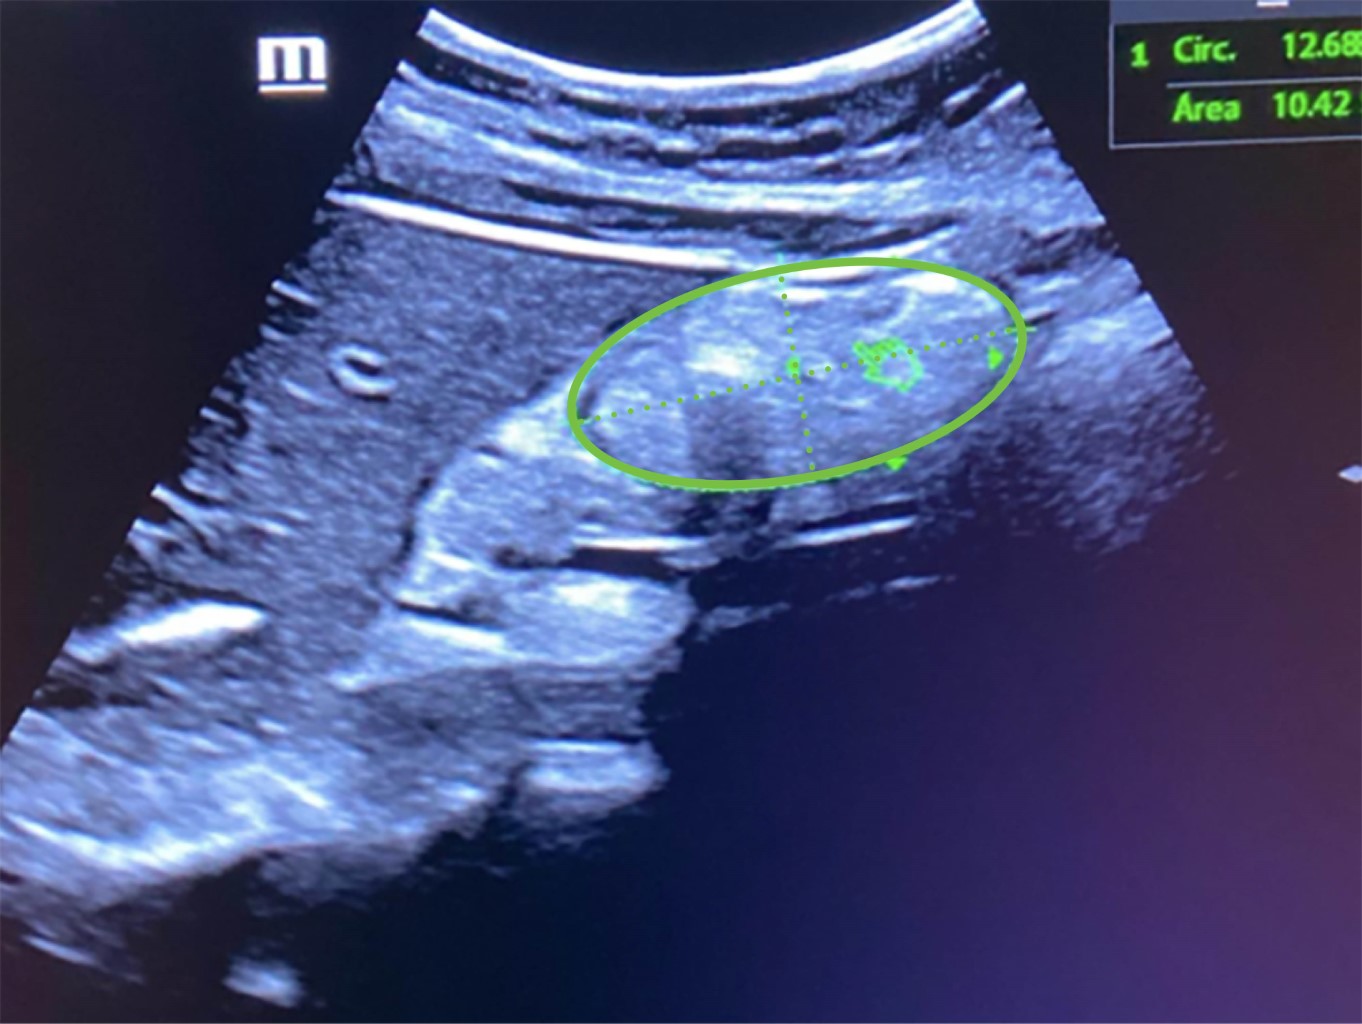

Previo al procedimiento endoscópico, se colocó al paciente en decúbito lateral derecho y se aplicó gel en la región epigástrica, se encendió el equipo de ultrasonido Butterfly iQ/iQ+™ y se seleccionó la configuración predeterminada vista de abdomen, se coloca la sonda universal del mismo equipo de ultrasonido sagitalmente en la región epigástrica, se realizó un barrido en dicha región, inicialmente girando en sentido de las manecillas del reloj y después en contra de ellas, también desplazándose en sentido cefálico y caudal con la finalidad de obtener la vista más adecuada de la región transversal del antro gástrico para realizar una medición de su área transversal abarcando todo el espesor de la pared gástrica (Figura 1), posteriormente de acuerdo a la fórmula de Perlas12 (27.0 + (14.6 × (área transversal del antro gástrico en centímetros)) − (1.28 × edad)) se obtuvo el volumen de contenido gástrico. Este procedimiento fue replicado por dos únicos residentes del servicio de anestesiología, a continuación, se realizó procedimiento endoscópico como previamente había sido planeado por el servicio de gastroenterología aspirando el contenido gástrico total para ser medido. Ambos residentes de anestesiología fueron cegados entre sus mediciones obtenidas y el contenido aspirado por endoscopia, siendo recolectados los datos por un cuarto integrante del grupo de investigación. Para el análisis de datos se utilizó el software Stata versión 14 (StataCorp LLC software, Texas, EE. UU.). Las variables continuas y categóricas se expresaron como medidas de tendencia central. Se obtuvo el índice de κ ponderado para ver el nivel de concordancia entre los resultados medidos entre los usuarios de ultrasonido. Posteriormente se realizó un promedio de los volúmenes obtenidos por ultrasonido entre ambos usuarios, y se obtuvo la correlación por coeficiente de Pearson entre lo medido por ultrasonido promedio y lo aspirado por endoscopia, así como lo medido por ultrasonido promedio y las horas de ayuno, y por último la medición de contenido gástrico y las horas de ayuno. El criterio de significación estadística fue p < 0.05.

Figura 1